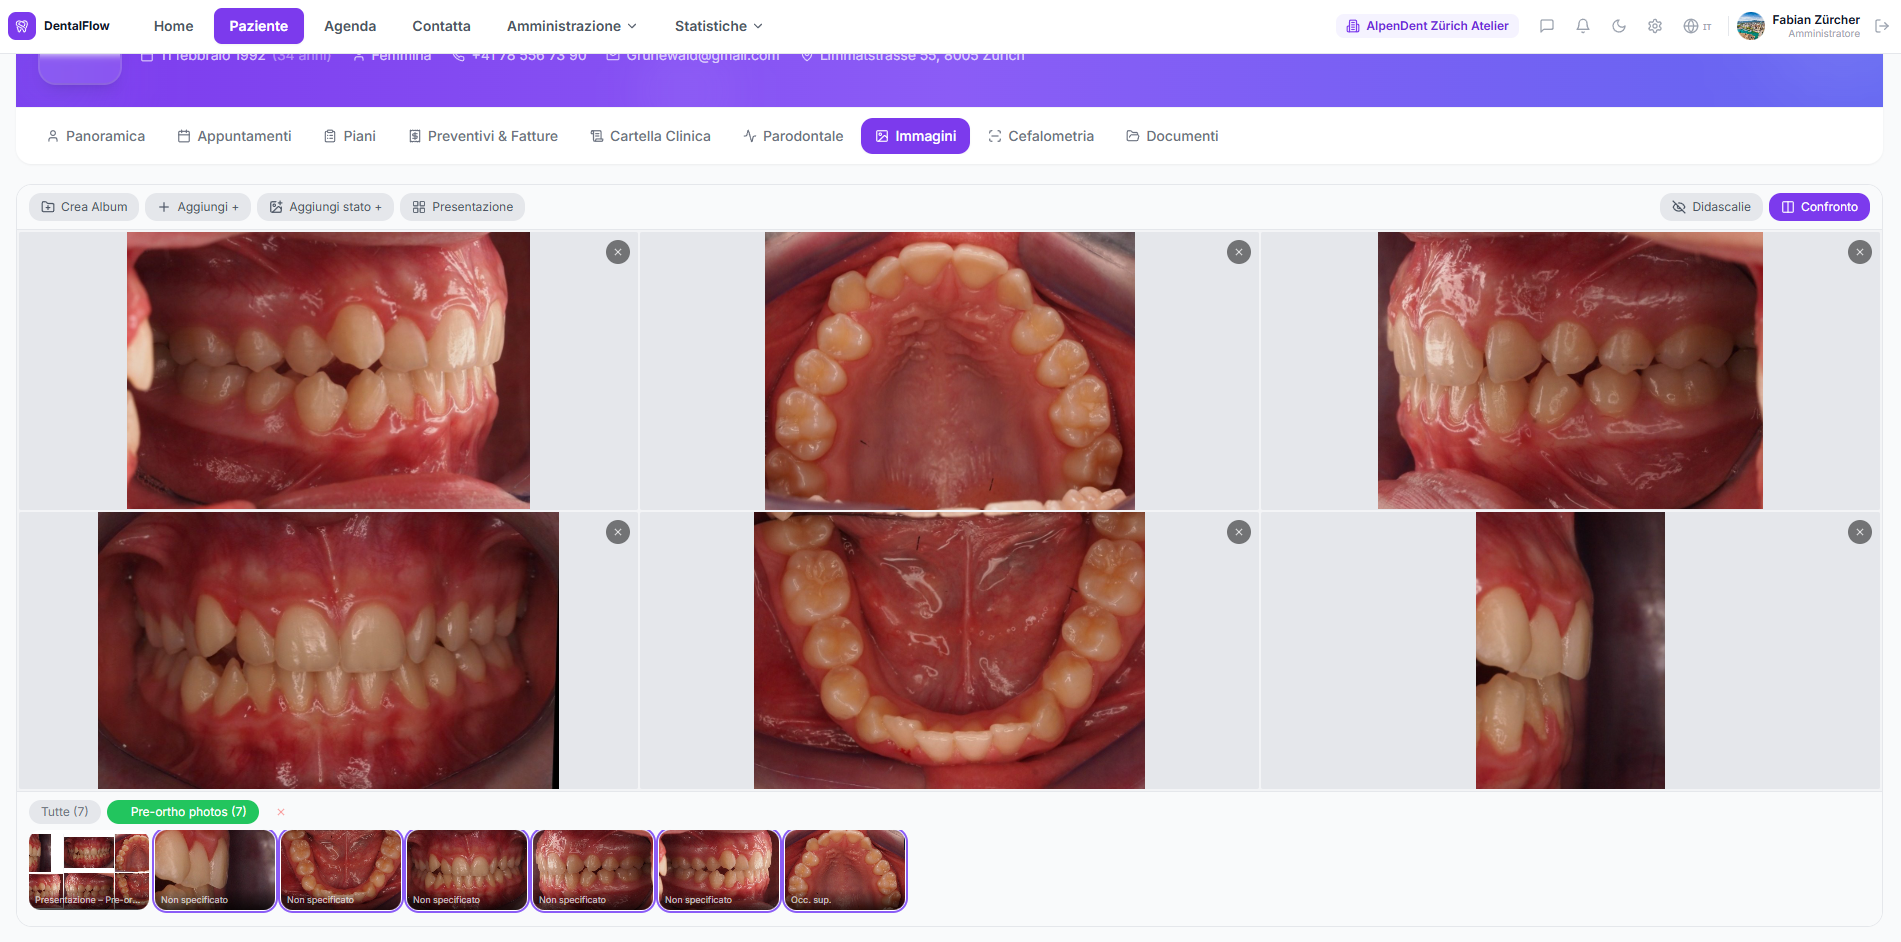

Stato fotografico completo del paziente: foto intra e extra-orali, album organizzati, confronto side-by-side.